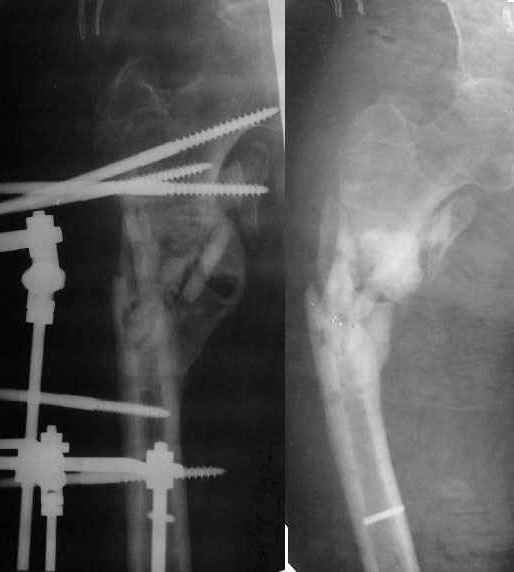

Неудачный остеосинтез пластиной: поломка винтов. После удаления сформирался гиполастический ложный сустав. Остеосинтез АВФ, циклическая компрессия-дистракция в области ложного сустава привела к формированию хорошей рентгенологической костной мозоли. Через 1,5 месяца ходил в аппарате без дополнительных средств опоры. Через 6 месяцев после клинической пробы - демотаж. Через 4 месяца после демонтажа - лизис костной мозоли, рецидив деформации.